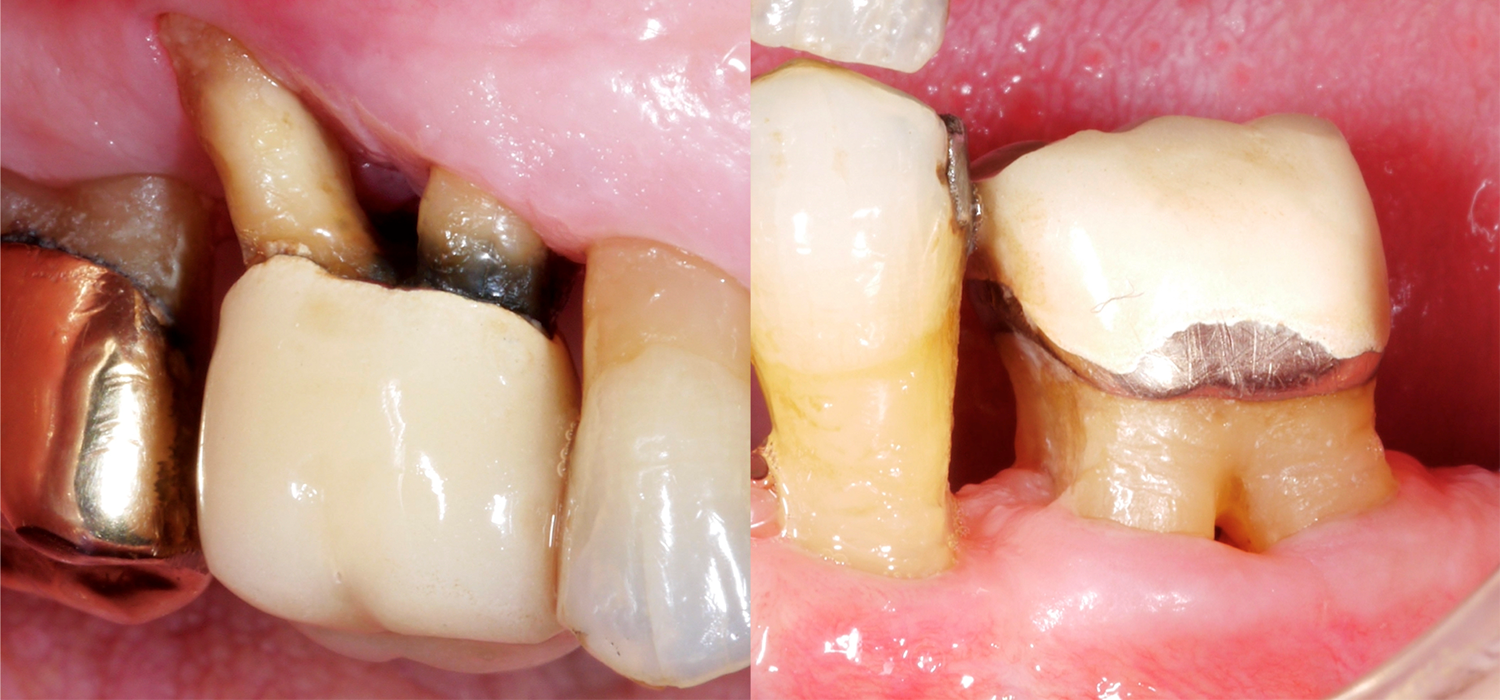

When it comes to teeth, those with multiple roots are, of course, often much more difficult to treat, especially if they present furcation defects. Why is the furcation area so challenging? In comparison to single-rooted teeth, access for mechanical cleaning of the root surface is much more difficult, the furcation entrance can often be very small/narrow, and there may also be further anatomical particularities, such as enamel projections.

A recently published study from Frankfurt (Eickholz 2021) specifically looked at teeth with a through-and-through furcation defect. They studied a total of 265 teeth with a through-and-through furcation defect in 160 patients; all patients had been receiving periodontal maintenance treatment for at least five years. We should take the following important points into account based on this data:

- Teeth with a grade III furcation defect are more frequently lost than single-rooted teeth, for example, and, after approx. 10 years of periodontal maintenance treatment, we should expect approx. one third of these teeth to have been extracted. At the same time, however, this also means that two thirds of these periodontally severely compromised teeth are still in place.

- There is a wide range of possible reasons for an extraction – from periodontal problems, through to cavities and/or prosthetic problems.

- The following risk factors for loss have been identified for teeth with a through-and-through furcation defect: a higher level of bone loss at the start of the treatment and higher probing depths at the start of the maintenance treatment.